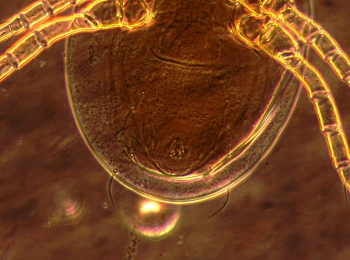

以下圖片是醫生在生物顯微鏡下發現他的睫毛根部居然有螨蟲在蠕動。看到顯示屏上蠕動的蟲體時,著實嚇了一跳。

螨蟲體型細小,在顯微鏡下是半透明的,普通生物顯微鏡很難看清楚,明美倒置顯微鏡MI52-N支持相襯觀察,能讓螨蟲輪廓和細節更清晰地呈現出來。

明美倒置顯微鏡下捕捉下塵螨